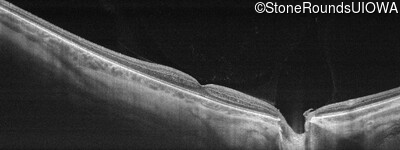

Age at visit: 26 years

This 26 year old man had significant myopia since childhood and uncorrectable reduction of acuity since his mid teens. Optic nerve abnormalities were noticed on a routine exam at age 5 and a diagnosis of Retinitis Pigmentosa was suggested. His medical history is also positive for profound hearing loss at birth and type 1 diabetes mellitus.

Age at visit: 29 years

Age at visit: 30 years